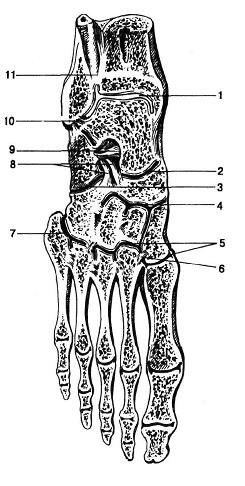

Анатомия суставов Шапарова и Лисфранка: фото и информация